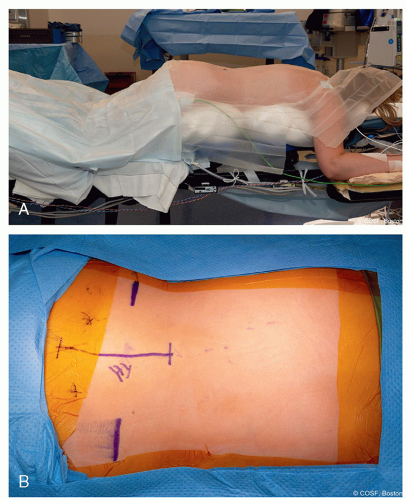

Positioning

Prone on radiolucent table (Figure 7.1A)

Flex hips to reduce anterior pelvis tilt and lumbar lordosis (Figure 7.1B)